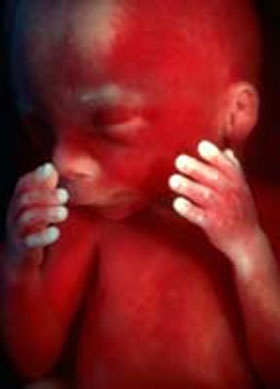

Фото плода на 19 неделе беременности (возраст плода 17 недель)

Кожа малыша становится менее красной, морщины разглаживаются благодаря накоплению подкожного жирового слоя. Жир в первую очередь откладывается в области груди, шеи и вокруг почек. На поверхности кожи сохраняется защитная смазка, которая предохраняет ее от раздражений и помогает сохранять тепло. На кончиках пальцев уже проявляется уникальный рисунок – завитки, улитки и волны, который у каждого человека индивидуален, и малыш уже мог бы пройти исследование на отпечатки пальцев.

Кости ребенка укрепляются, хрящи постепенно затвердевают, а конечности становятся более пропорциональными по отношению к туловищу.

На данном этапе вес плода, как правило, составляет около 250-300 граммов. Длина малыша достигает 25 сантиметров, а размеры головы составляют 43,1 мм, живота – 43,2 мм, и грудной клетки – 43 мм.